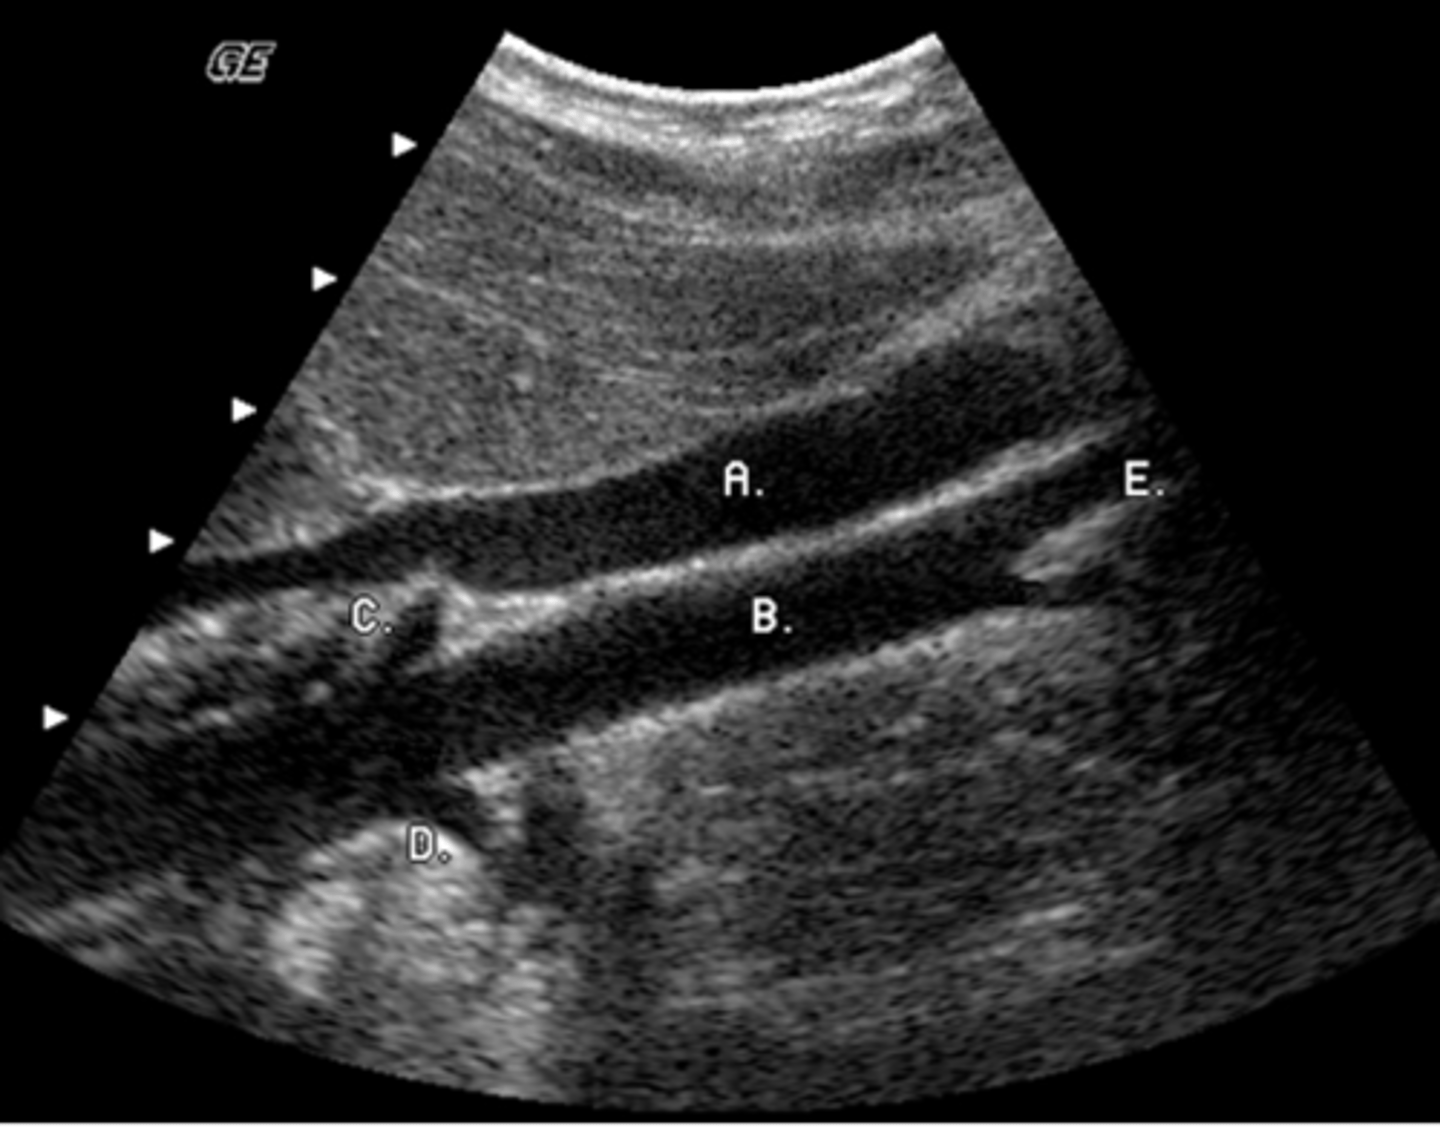

e. Inferior vena cava

Identify the anatomy labeled "C"

a. aorta

b. portal vein

c. superior mesenteric vein

d. inferior mesenteric vein

a. left lobe

What lobe of the liver does the letter A represent?

b. caudate lobe

c. posterior right lobe

d. anterior right lobe

e. quadrate lobe

e. caudate lobe

The arrow labeled D is pointing to what lobe of the liver?

a. medial segment of left lobe

b. lateral segment left lobe

c. posterior segment right lobe

d. anterior segment right lobe

b. aorta

What vessel is seen posterior to the vessel labeled D?

a. IVC

c. right renal artery

d. IMV

e. splenic vein

b. internal jugular vein

Identify the structure labeled E

a. common carotid artery

c. external jugular vein

d. longus coli muscle

e. subclavian vein